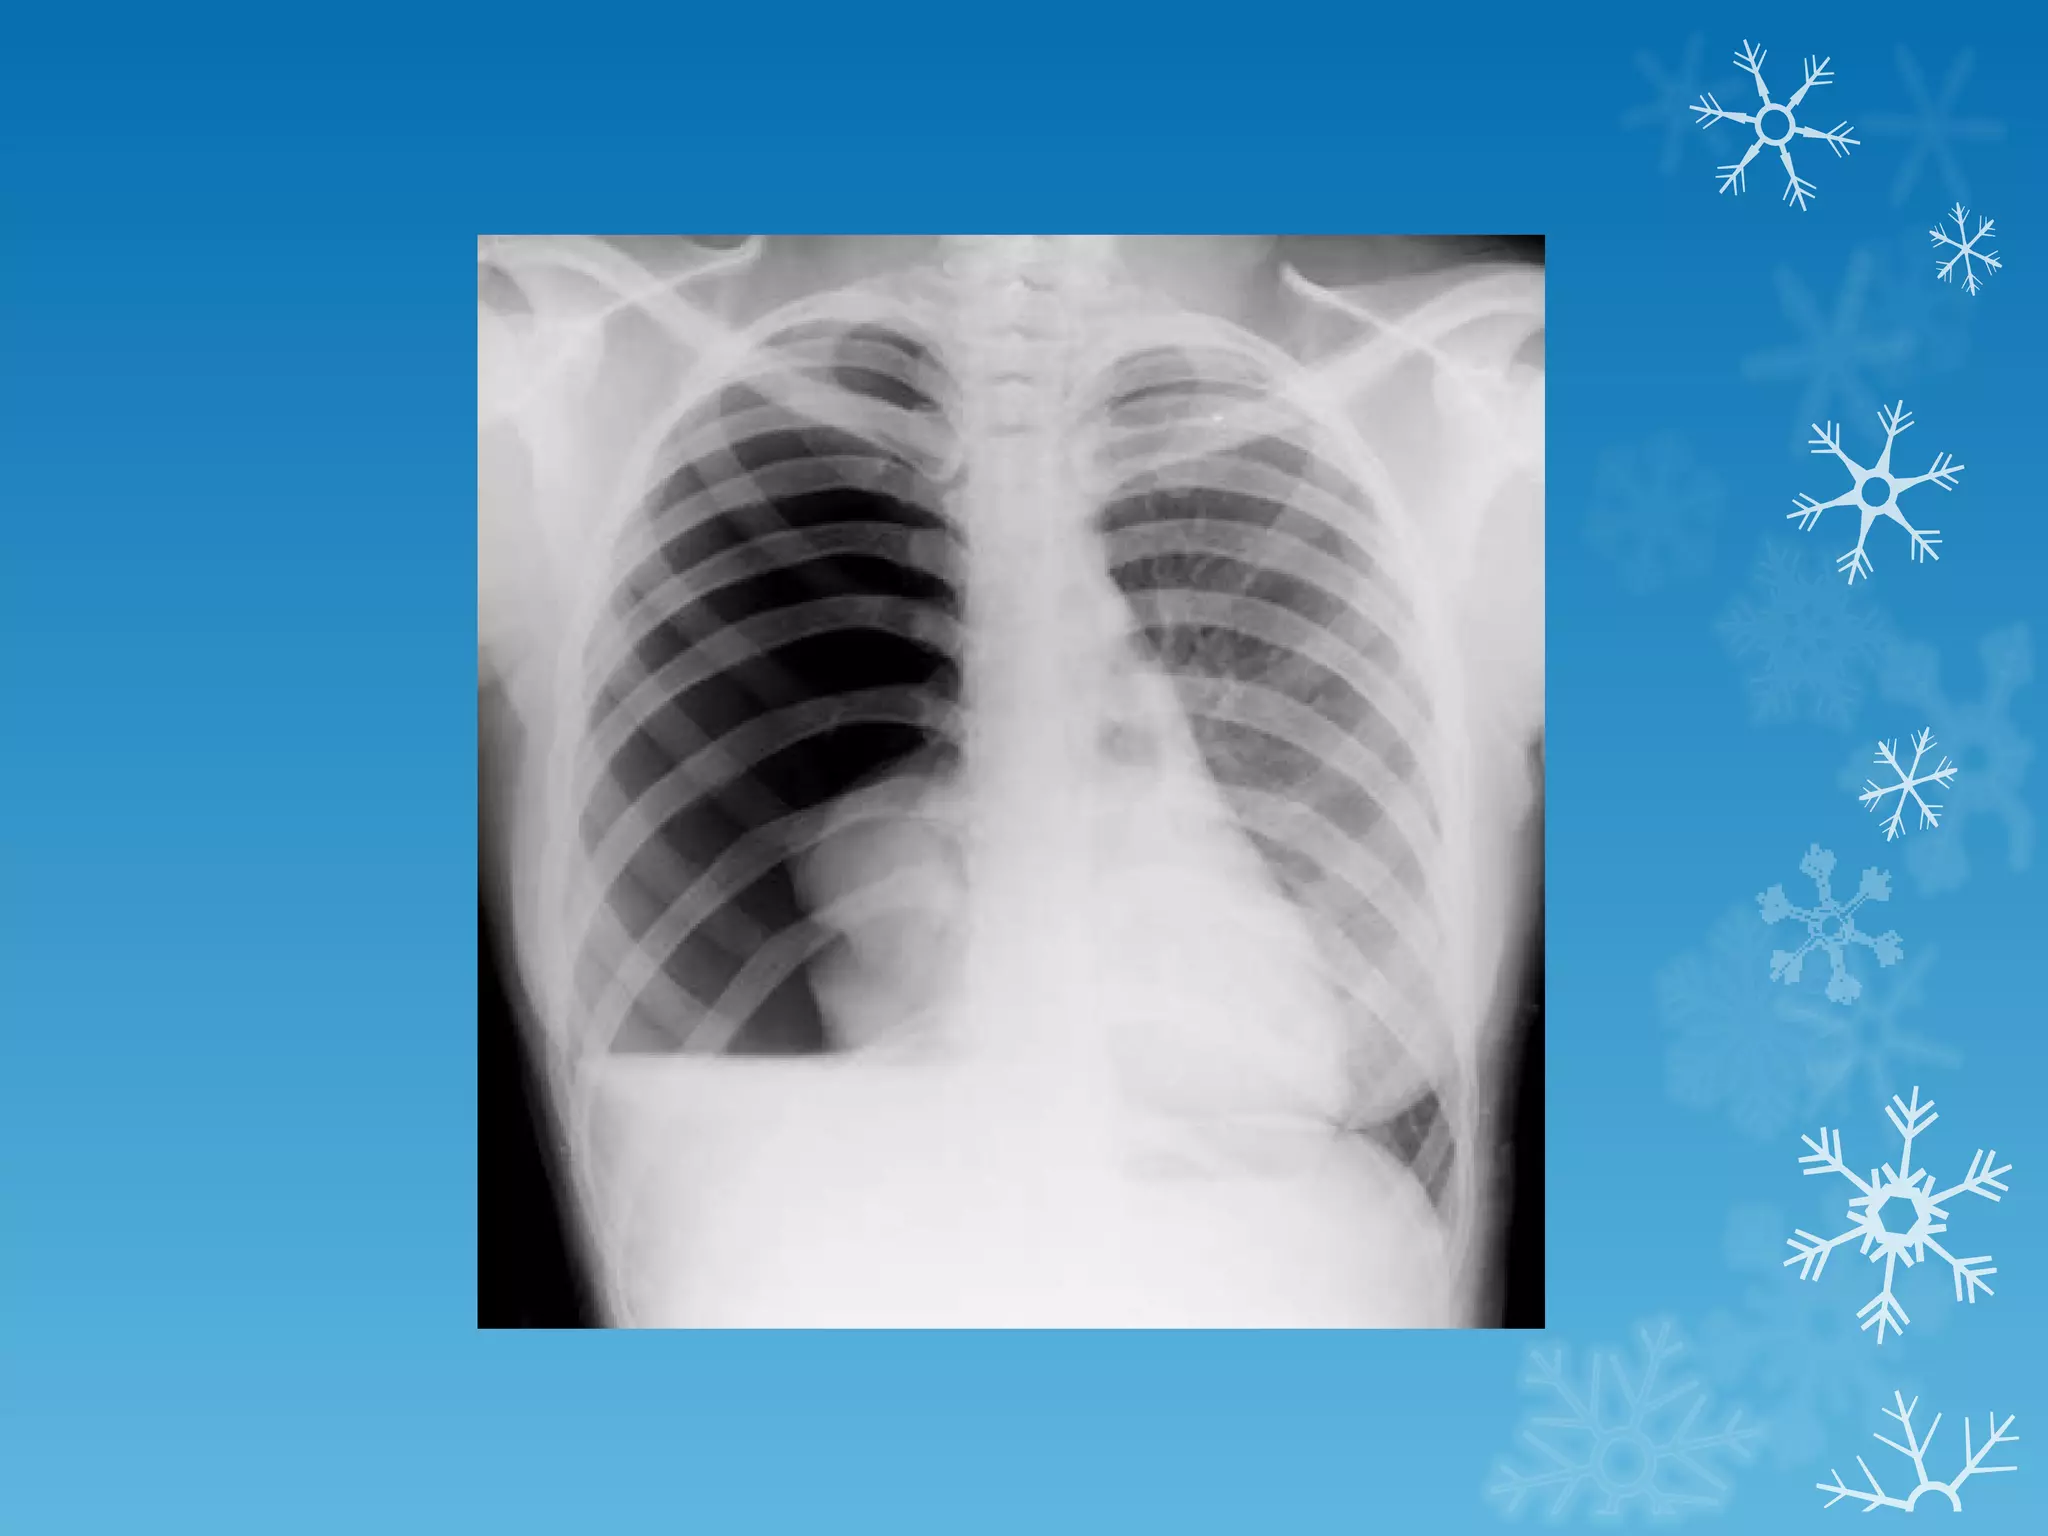

This document discusses chest x-ray interpretation and provides guidance on evaluating x-rays. It explains that tissue density determines how an x-ray beam penetrates, with denser tissues appearing whiter and less dense tissues appearing blacker. It also outlines different chest x-ray views and factors to consider like patient orientation, age, gender, and rotation. Abnormalities are described as appearing too white, too black, too large, or in the wrong place. The document stresses a systematic approach of identifying, localizing, describing lesions, and providing differential diagnoses.